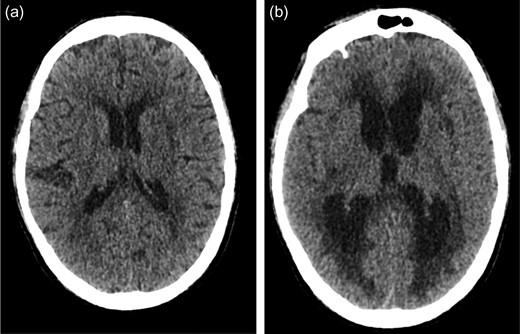

An 80-year-old man with a background of hypertension, gout, osteoarthritis and cerebrovascular disease presented following an injury to his left big toe. He developed confusion and sepsis secondary to deep infection of his left big toe. As part of the initial septic screen, he had a CT scan which did not show any evidence of hydrocephalus (Fig. 1a). He was started on intravenous antibiotics and the decision was made to undertake amputation of the infected toe. After extubation, he had persistently reduced level of consciousness. A CT head scan performed post-operatively showed new onset acute hydrocephalus with no evidence of haemorrhage or infarction (Fig. 1b).

(a) Initial CT head scan performed did not show evidence of hydrocephalus. (b) Post-operative CT head showing new onset acute hydrocephalus.